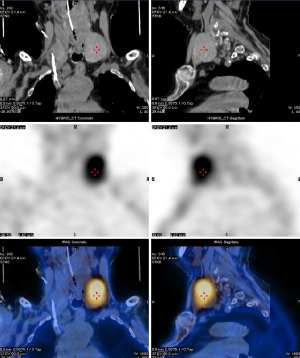

In this study, four patients with functional parathyroid carcinoma underwent preoperative ultrasound (Figure 1) and dual-phase technetium 99m sestamibi (99mTc-MIBI) parathyroid scintigraphy with single-photon emission computed tomography (SPECT)/computed tomography (CT) (Figure 2). The two patients with nonfunctional parathyroid carcinoma had preoperative ultrasound and CT scans (Figure 3). There were 2 cases where the tumors were located in the right neck and 4 cases in the left neck. On ultrasound examination, the smallest tumor measured 2.5 cm in diameter, while the largest was 11.4 cm, with five cases (83.33%) having diameters ≥3 cm (Table 2). Among the four patients with functional parathyroid carcinoma, preoperative PTH levels ranged from 269.8 to 6,012.3 ng/L, with three cases exceeding 10 times the upper limit of normal. All four patients had preoperative serum calcium levels above the upper limit of normal. In contrast, the two patients with nonfunctional parathyroid carcinoma had normal preoperative PTH and calcium levels (Table 2).

The diagnosis of parathyroid carcinoma is extremely challenging, especially preoperatively (18,19). Functional parathyroid carcinoma presents clinically with symptoms identical to those of hyperparathyroidism caused by parathyroid adenomas, making differentiation between the two difficult. Some researchers found that when PTH levels exceed 10 times the upper limit of normal (3) or when serum calcium levels are greater than 3 mmol/L in conjunction with a parathyroid tumor diameter larger than 3 cm, a diagnosis of parathyroid carcinoma should be highly considered (19). In this study, PTH levels exceeded 10 times the upper limit of normal in three cases (50%), and serum calcium levels were greater than 3 mmol/L with tumor diameters larger than 3 cm in two cases (33.3%). However, these characteristics are also present in many parathyroid adenomas and therefore cannot serve as the sole diagnostic criterion. Parathyroid carcinoma may appear as a larger tumor with a diameter often exceeding 3 cm or with unclear margins on ultrasound, CT, or magnetic resonance imaging (Figures 1-3). However, these features can also be observed in parathyroid adenomas. Thus, while imaging studies can help detect and localize parathyroid tumors, diagnosing parathyroid carcinoma based solely on imaging is extremely difficult (20). Most cases of parathyroid carcinoma are diagnosed through postoperative histopathological examination, as was the case with all six patients in this study.